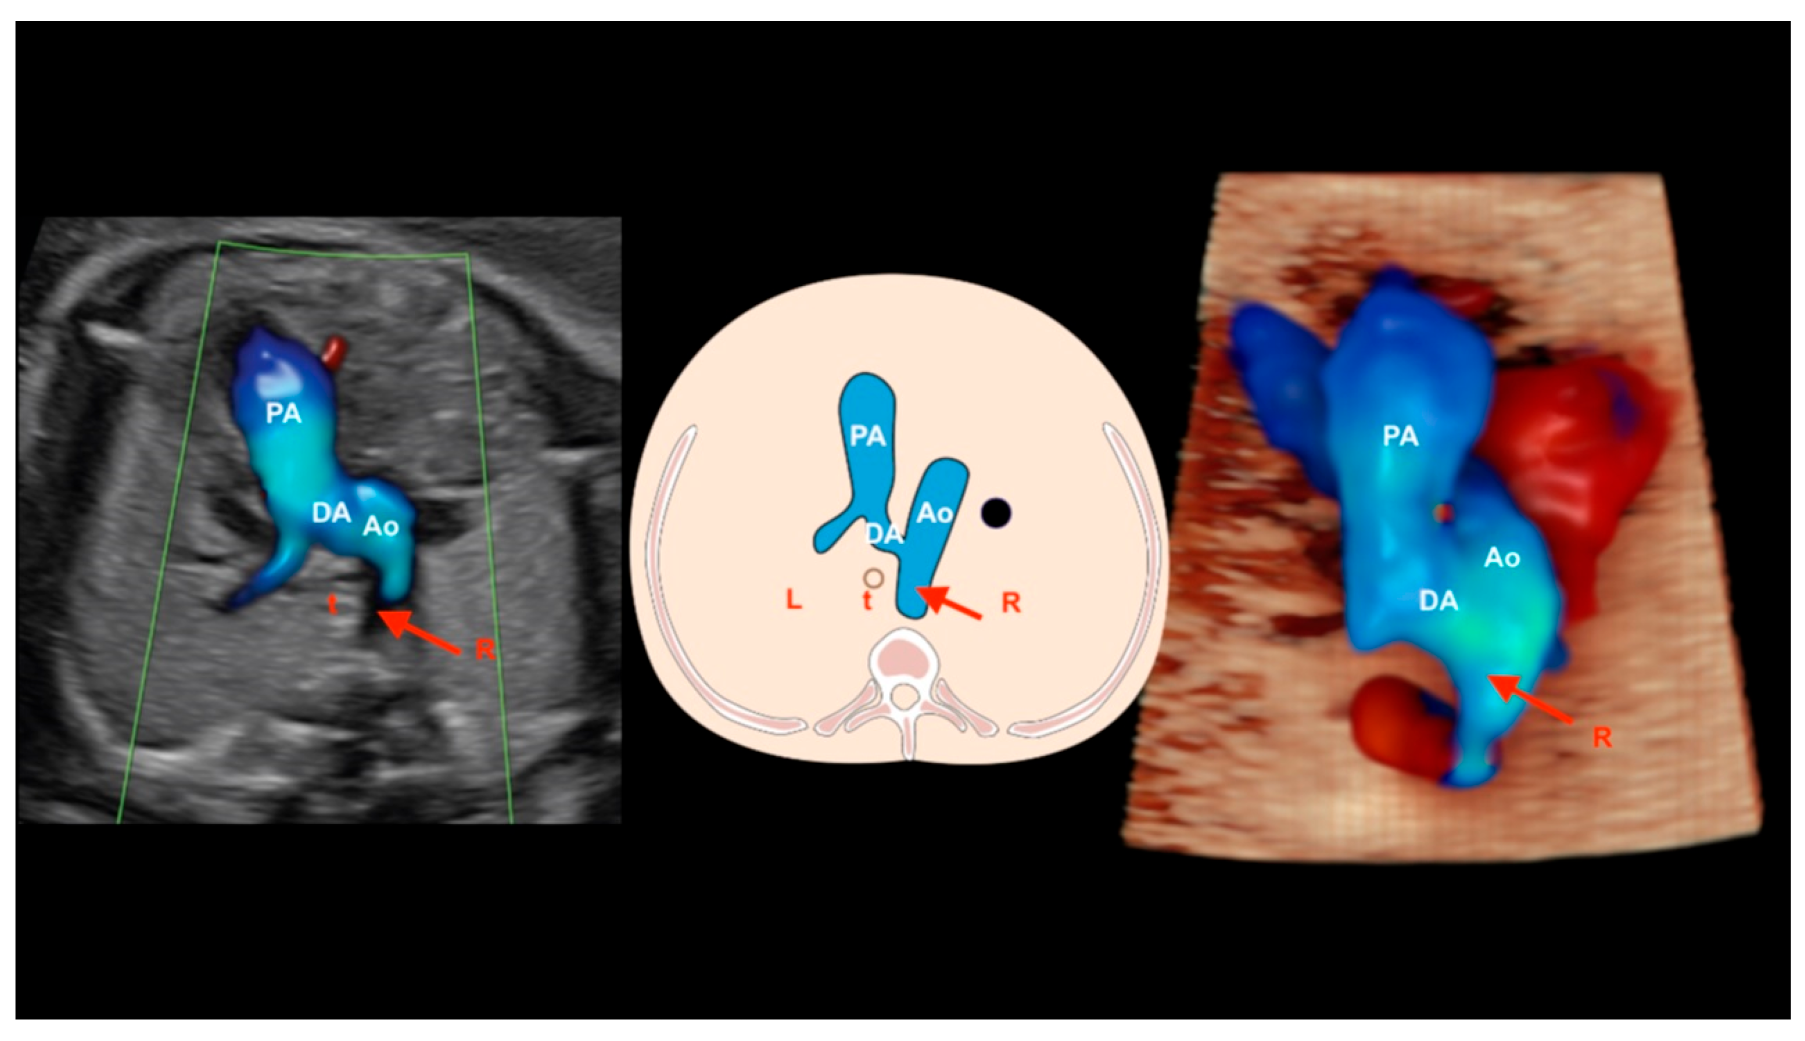

11. Anomalous Venous Return